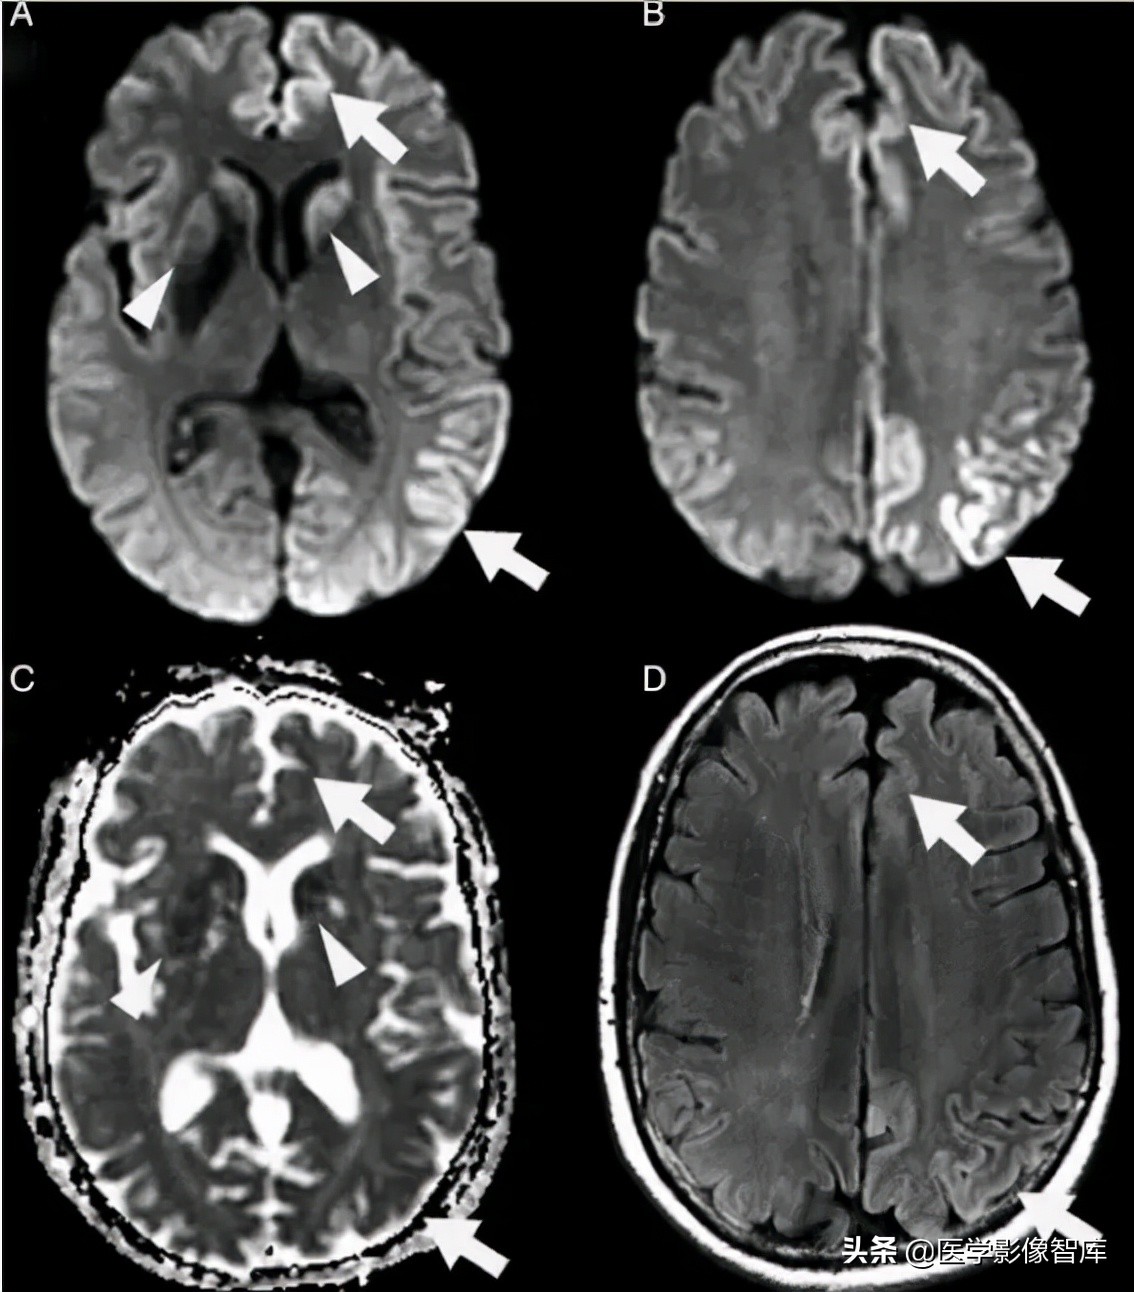

图 2 42 岁女性,延长的亚临床癫痫持续状态患者所做的两次头颅 MR 结果。A 为 T2WI,B、C、F 为 DWI,D 为 ADC 图,E、G 为 FLAIR,可见发病 4 天时双侧顶枕叶可见明显 DWI 高信号病灶,T2 相也为高信号,ADC 低信号,发病 25 天时,病灶消失

图 3 花边征(飘带征),散发型 CJD 患者,A、B 为 DWI,C 为 ADC 图,D 为 FLAIR。可见患者双侧皮层不对称的 DWI 高信号(箭头),基底节区 DWI 高信号(三角箭头),病灶 ADC 图上为低信号,FLAIR 上高信号